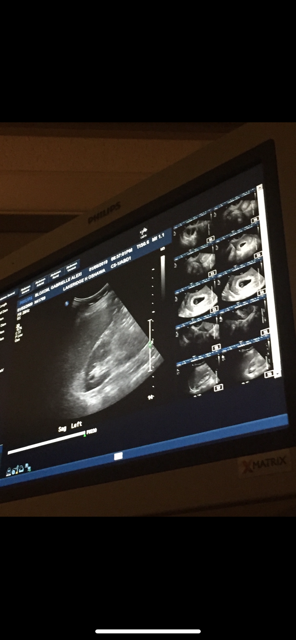

Boy or girl angel baby?

So I’m currently expecting my rainbow babygirl however I had a miscarriage last May and my partner and I always wonder if she has an angel big brother or sister?

What would you guess our angel baby is a boy or girl?

6w2d